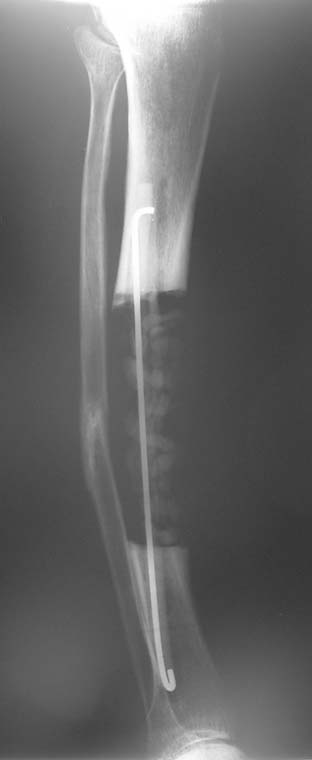

Eksternal fiksatör ile geçen süre (eksternal fiksasyon indeksi), gereken distraksiyon miktarına bağlıdır ve bu süre boyunca bazı komplikasyonlarla karşılaşılabilir. Distraksiyon dönemi sona erdikten sonra, distraksiyon süresinin iki katını aşan konsolidasyon döneminde hastalar eksternal fiksatörü zorlukla tolere edebilirler. Yeterli konsolidasyon sağlanmadan eksternal fiksatör çıkartılırsa ise kırıklar, deformite ve kısalık oluşabilir. Hastanın fiksatör ile birlikte geçirdiği sürenin azaltılması ve böylece hasta konforunun ve aktivite düzeyinin arttırılması için intramedüller çivi üzerinden uzatma yöntemi uygulanmaktadır. Bu yöntemde distraksiyon dönemi sona erdiğinde kemiğin içindeki çivi statik olarak kilitlenmekte ve eksternal fiksatör çıkartılmaktadır. Stabilizasyon intramedüller çivi tarafından sağlandıktan sonra konsolidasyon dönemi gerçekleşmektedir. Bu şekilde hem eksternal fiksatörün uzun süre kalmasından hem de erken çıkartılmasından kaynaklanan komplikasyonların önüne geçilmektedir.

Vaka 1